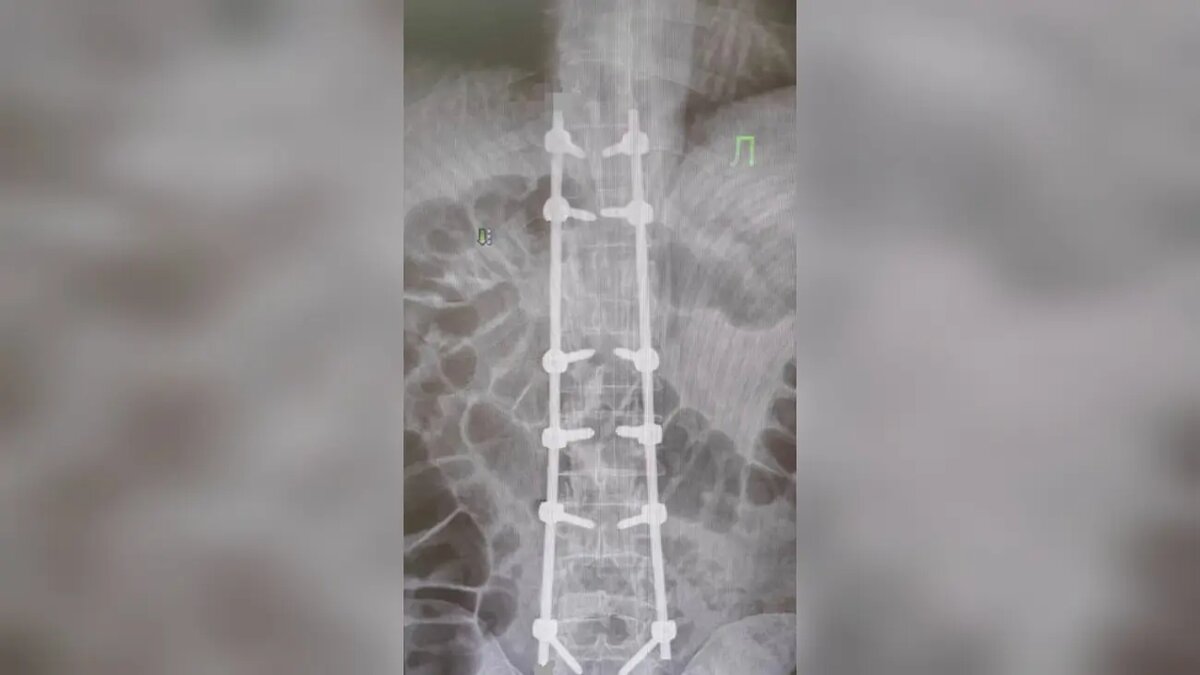

Во время вмешательства был использован метод хирургической стабилизации позвоночника. Через специальные анатомические структуры — ножки позвонков — в повреждённые сегменты были установлены титановые винты, соединённые прочными металлическими стержнями. Конструкция создаёт надёжный внутренний «корсет», который фиксирует позвоночник, снимает давление с нервных структур и способствует восстановлению костной ткани.

«Оперативное вмешательство прошло без осложнений. Уже на вторые сутки после вмешательства пациент смог вставать и самостоятельно передвигаться в пределах палаты и отделения», — отметил собеседник.